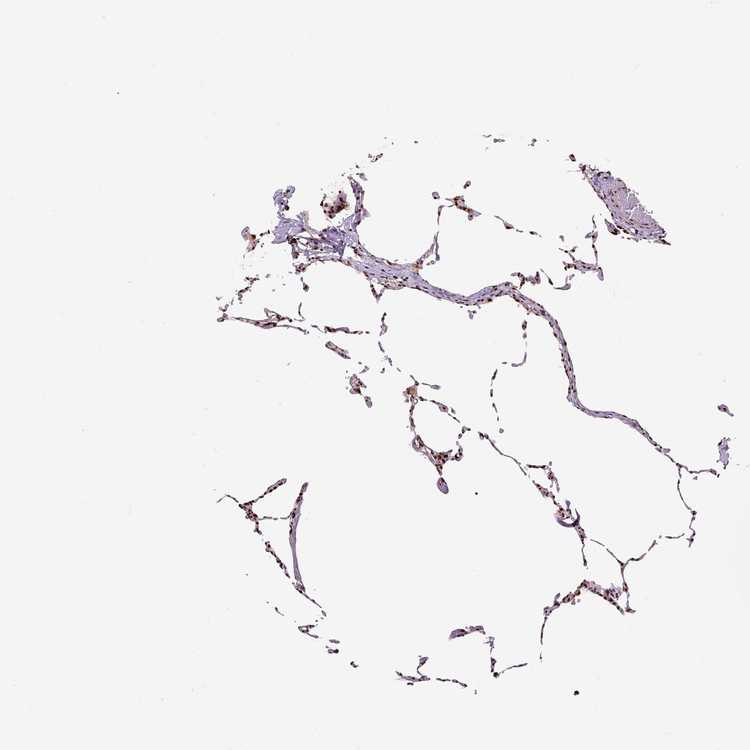

LUNG - Antibody stainingi

Antibody staining in the annotated cell types in the current human tissue is reported as not detected, low, medium, or high, based on conventional immunohistochemistry profiling in selected tissues. This score is based on the combination of the staining intensity and fraction of stained cells.

Each image is clickable and will lead to virtual microscopy that enables deeper exploration of all samples and also displays staining intensity scores, fraction scores and subcellular localization as well as patient and tissue information for each sample.

Antibody HPA021238Antibody HPA062245Antibody CAB069927

Alveolar cells High-High

Alveolar cells type I -Medium-

Alveolar cells type II -Medium-

Endothelial cells -Medium-

Macrophages HighMediumHigh